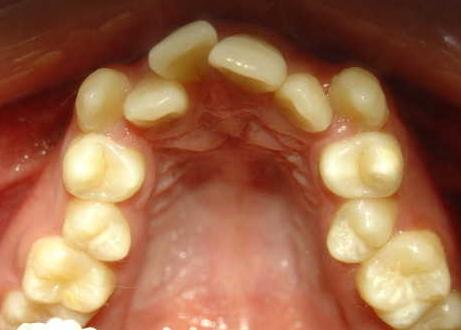

2、乳牙滞留或掉太快、磨损不够

这种情况可能会影响恒牙的发育和位置;

如出现双排牙,通过及时拔牙即可恢复到健康的状态;乳牙早失一旦发生,也可以通过检查来做间隙保持;龋齿等口腔问题更要及时处理。